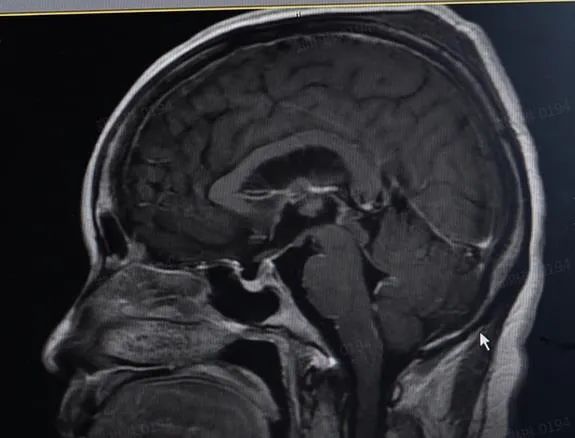

接诊医生结合患者的病史和体征,认为是颅内感染的可能性较大。最终,在患者的脑脊液及血清中找到了李斯特菌,进一步证实了医生的判断。给予抗感染等对症治疗后,陈女士的症状逐渐好转。